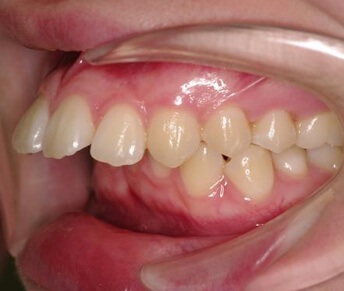

- 裏側からの矯正装置

(リンガルブラケット装置)

メリット

- ・装置が見えない。

デメリット

- ・構造的に装置と装置の間隔が狭い為ワイヤーの弾力を利用しにくいので歯を並べるのに時間がかかり、治療期間が長くなる。

- ・舌を動かしにくいので、正しい発音が出来ない。

- ・装置が舌に当たり舌に口内炎ができ易いので、食事に苦労する。

- ・歯みがきがしにくく、歯周病になりやすい。

- ・装置が裏側になるのでゴムやヘッドギアなどが使いにくいため、良い治療結果を得る事が難しい。

- ・裏側に装置があるので治療操作がし難く、毎回の治療時間が長く必要になる。

- ・装置自体が高価なのと、治療時間が長くかかるので治療費が高額になる。